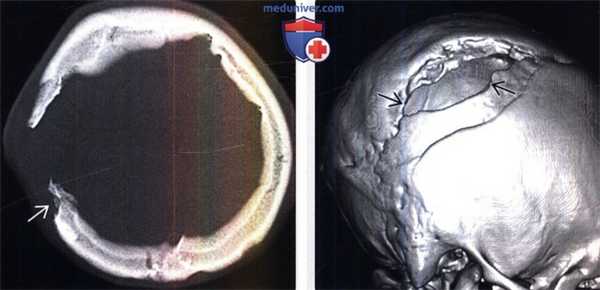

(Слева) КТ, костное окно, аксиальный срез: отмечается, что кортикальный слой краев дефекта черепа хорошо выражен. Обратите внимание на фестончатость наружной пластинки кости свода черепа.

(Справа) КТ, костный режим, 3D реконструкция в режиме оттененных поверхностей: визуализируется расширенный дефект черепа с фестончатыми краями. По поводу данного «растущего» перелома черепа с лептоменингеальной кистой было проведено оперативное лечение.